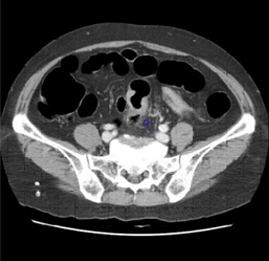

CT CT 이미지

• CT 대장 조영술

CT 대장 조영술 검사는 컴퓨터 기술과 영상의 눈부신 발전에 힘입어 대장암의 새로운 검사법으로 주목받고 있다. 정확한 검사를 위해 대장을 비우는 것이 필수적이므로 대장 내시경과 같은 방법으로 하제를 이용해 장을 비워야 한다. 검사는 항문에 튜브를 삽입하고 공기나 이산화탄소를 주입하여 장을 부풀려서 CT 촬영하여 영상을 얻고, 이 영상들을 컴퓨터에서 3차원 영상 재구성 소프트웨어를 이용하여 마치 내시경으로 대장 내부를 보듯이 가상의 이미지를 만들어내어 대장을 관찰 하게 된다.

CT 대장조영술의 장점은 안전하고 검사시간이 매우 짧다는 점이다. 장 천공이나 출혈 등의 합병증이 거의 없고 대장 내시경처럼 통증을 줄이기 위해 안정이나 수면유도제를 사용할 필요가 없기 때문에 10분에서 15분만에 검사를 끝내고 곧바로 집이나 직장으로 돌아갈 수 있다. 또한 고령이나 심장병, 신장병 등의 여러 가지 내과적인 질환을 앓고 있어 대장내시경 검사를 받기 어려운 경우에도 검사가 가능하다. 암으로 인해 대장이 막혀서 내시경이 통과하지 못하는 경우에도 상부 대장의 상태를 평가할 수 있으며, 일반 복부 CT 검사와 마찬가지로 대장뿐 아니라 배 속의 내부 장기 즉, 간, 담낭, 췌장, 비장, 신장 등의 다른 장기도 함께 검사할 수 있다.

그러나, 대장암을 진단하는 데는 우수하지만 대장 내시경에 비해 5mm 이하의 작은 용종 발견률이 낮고, 가끔 잔변과 암의 구별이 어려운 경우가 있으며, 환자가 방사선 조사를 받아야 하고, 암이나 용종이 발견되어도 조직검사를 할 수 없어 다시 대장내시경 검사를 받아야 하는 단점이 있다.

CT 대장조영술에서 발견된 대장암 CT 대장조영술에서 발견된 대장암 이미지